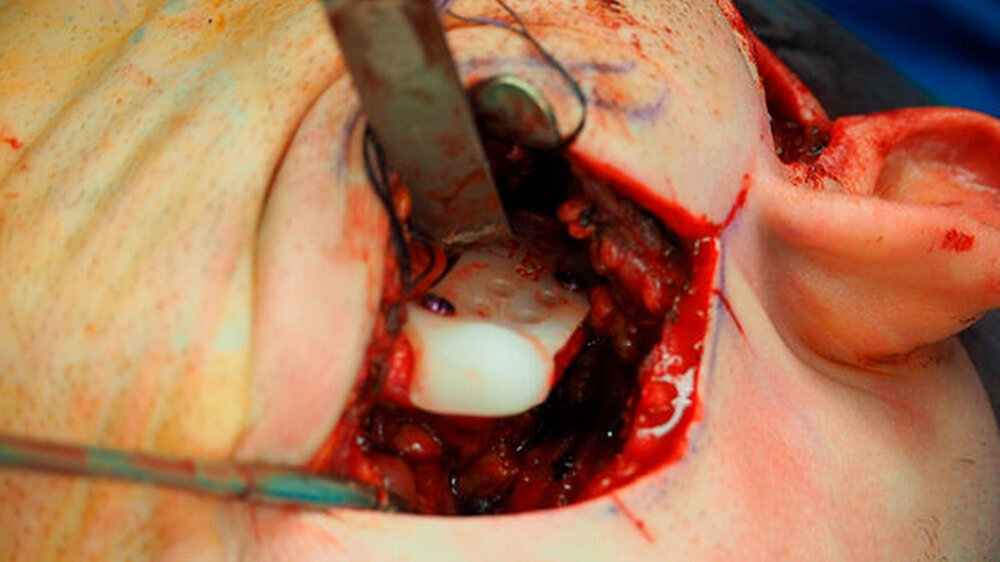

Nach Akzeptanz des Behandlungsplans wurden beidseits die TEPs (Totalendoprothesen) über jeweils einen präaurikulären und einen retromandibulären Zugang implantiert. Diese Prothesen wurden mit Schrauben mit exakt am CT-Datensatz definierten Schraubenlängen fixiert. Bei der Planung der Schraubenpositionierung wurde auch der Verlauf N. alveolaris inferior berücksichtigt und der Nerv geschont.

Vor der definitiven Fixierung der Prothesen wurden Dummys als Test eingesetzt, um eine optimale Positionierung der passgenauen finalen Prothesen zu erreichen (Abbildung 2 bis 9). Abbildung 10 a und 10b zeigen die postoperative Röntgenkontrolle.